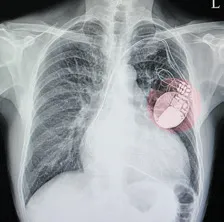

Cleveland Clinic researchers found only 14% of 344

patients with a pacemaker, implantable cardioverterdefibrillator

or biventricular pacemaker could answer

seven basic questions about their device. How much do

you know about yours?

If your heart isn’t beating normally, you may be one of millions who benefit from a cardiovascular implantable electronic device (CIED). These small, battery-powered devices implanted under the skin include pacemakers for speeding up slow hearts, implantable cardioverter-defibrillators (ICDs) for preventing sudden cardiac death and cardiac resynchronization therapy (CRT) devices, which help the heart contract […]